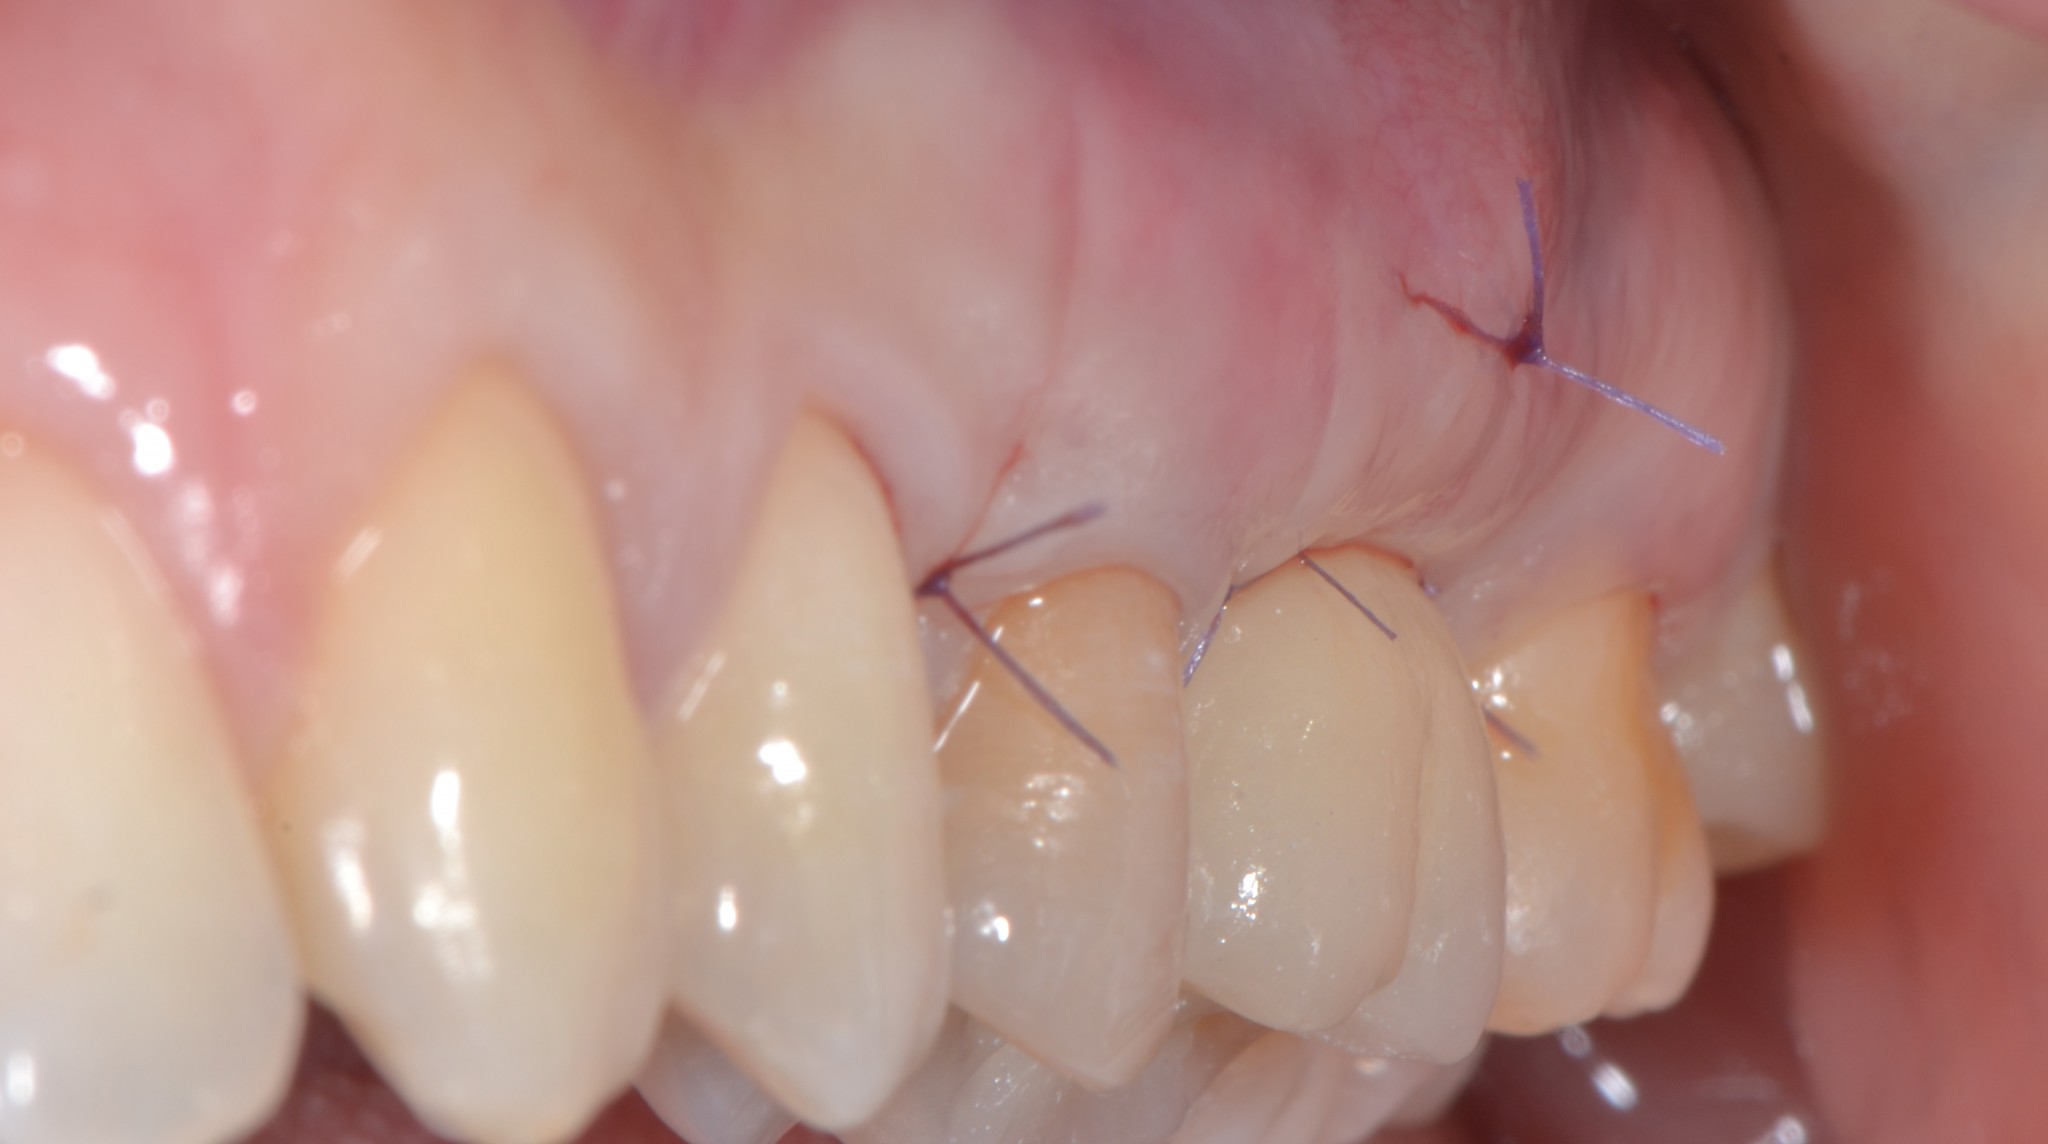

- Meno di 30 minuti di intervento (tempo controllato dagli orari delle foto)

- Fastidio al palato come se ti fossi bruciata con la pizza

- Possibilità di sanguinare un po’ dal palato (meno di quando ti sanguina il naso)

Guarda la foto alla fine dell’intervento, pensi che la paziente potrà avere grossi problemi?